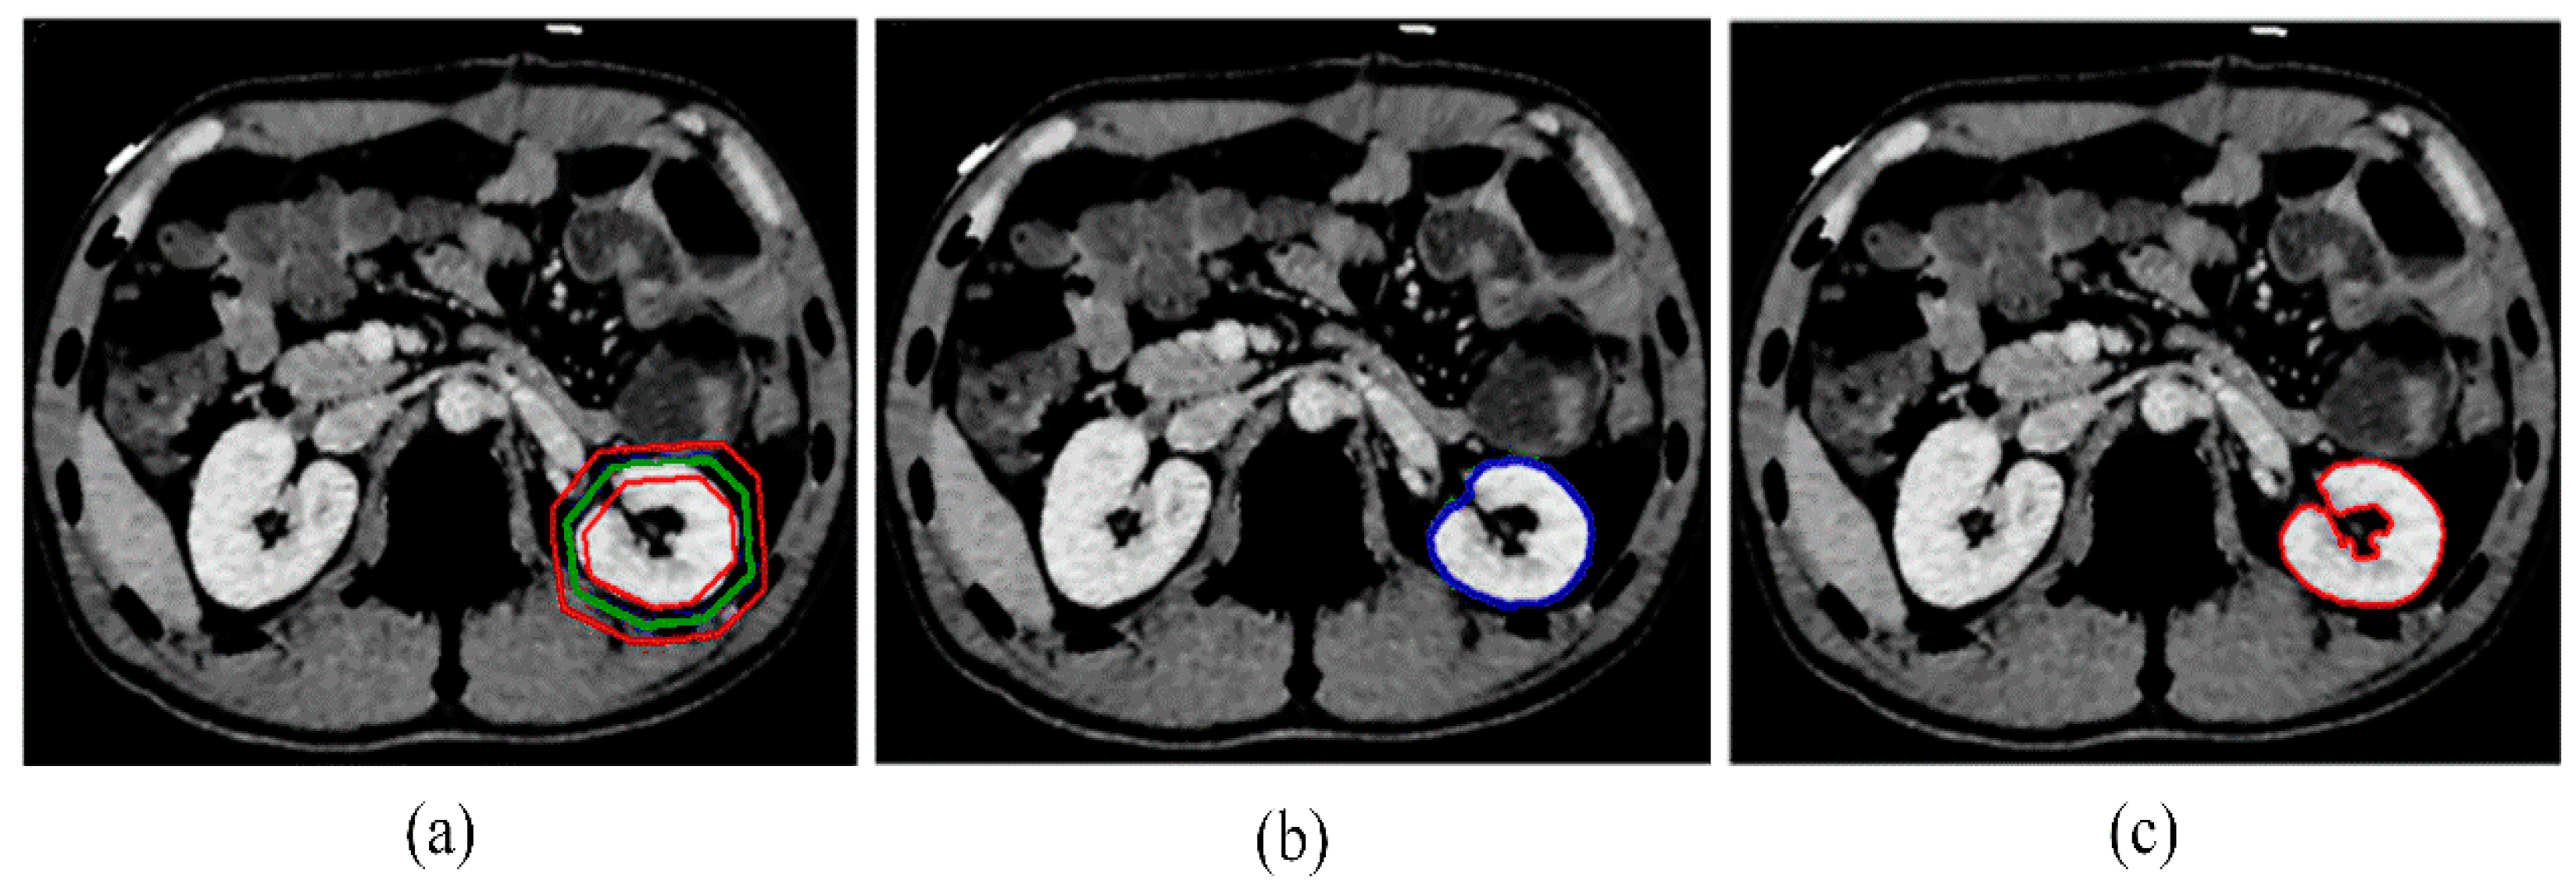

The GCBAC algorithm is efficient but struggles to evolve its contour to the concave areas of the target object. In Figure 11a, the green contour represents the initial contour, and the narrow band is the area between the two red contours. In Figure 11b, the blue contour represents the improved GCBAC segmentation result, while Figure 11c shows the manual segmentation result by experts. It is evident that the curve failed to evolve to the indentation of the kidney, primarily composed of adipose tissue. To address this issue, we incorporate postprocessing to the GCBAC result using the multi-regions volume histogram algorithm. Adipose tissue is low density and will cluster to the class with the smallest clustering center value. Therefore, removing this class from the GCBAC algorithm’s outcome will yield better results.

Figure 11. The evolution of GCBAC algorithm. (a) Initial contour is marked in green with its narrow band between red contours. (b) Modified GCBAC algorithm segmentation result is marked in blue. (c) Manual segmentation by experts is marked in red.